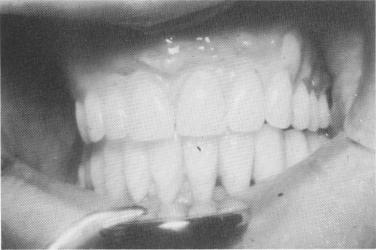

Fig. 11-145. The final prosthesis in place. Note open anterior flange in maxillary denture.

before the bridge was cemented, the posts were pre-pared parallel with each other.